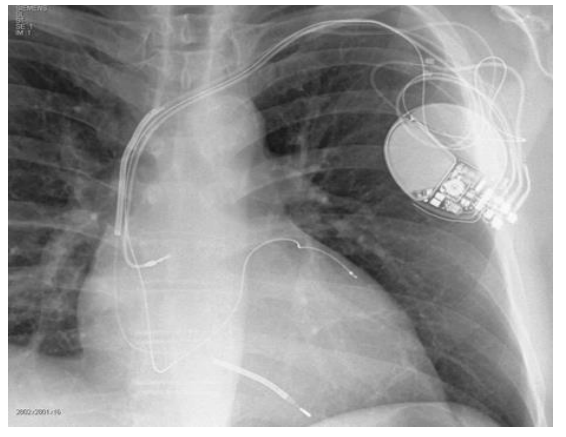

No contexto de pacientes com insuficiência cardíaca, assinale o caso descrito a seguir que teria maior benefício de receber o dispositivo observado na radiografia a seguir.

Enunciado 2982704-1

Abreviaturas: BRD: Bloqueio de ramo direito / BRE: Bloqueio de ramo esquerdo / FE: Fração de ejeção / IC: Insuficiência cardíaca / NYHA: New York Heart Association.